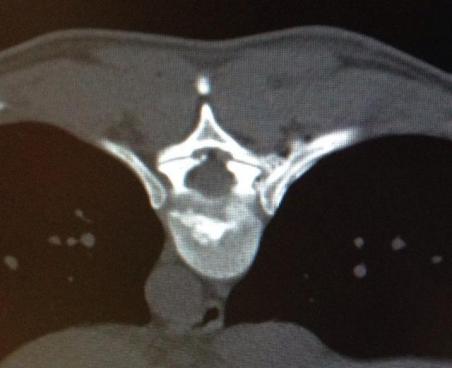

Hierbei wird unter Röntgenkontrolle eine dünne Nadel an die schmerzhaften Gelenke der Wirbelsäule geführt. Die anschließende Verödung der Nerven, welche die Schmerzen verursachen, erfolgt über eine Glasfaser.

Der Eingriff dauert etwa 15 Minuten und wird in örtlicher Betäubung und leichter Sedierung durchgeführt. Gerade die schwierige Behandlung der Ileosacralgelenke ist mit dieser Methode mit gutem Erfolg anzuwenden und vermeidet unnötiger Versteifungsoperationen. Er Effekt hält bis zu 4 Jahren an.